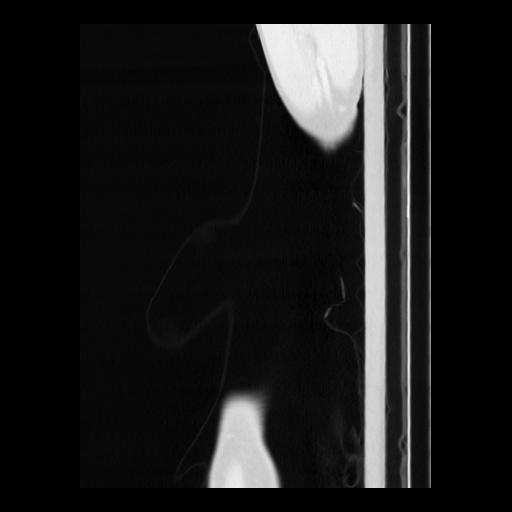

36 CUERPO,CE,Sagittal,3.000,CUERPO,Sagittal,